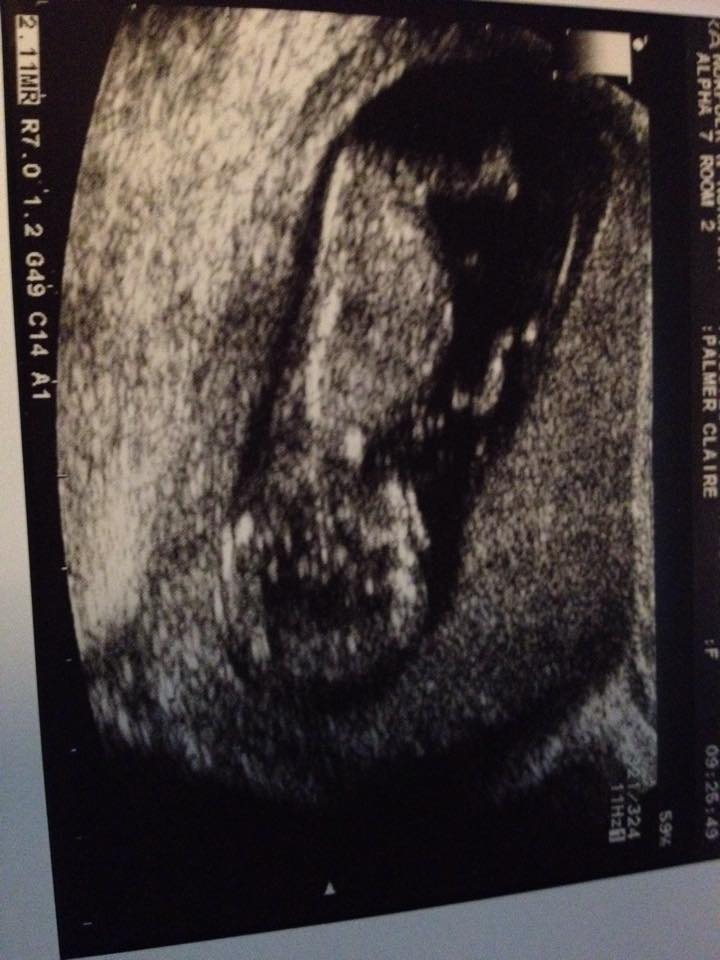

Hi ladies, someone from my Due in April group suggested here for gender guesses. So I figured I would pop my picture up here to see what people think.Attachment 21385

I don't see a clear nub.

I don't see a clear nub but see something that sways me pink x

No definite gender clues

Based on skull i would guess girl!

I cant see any clues, cute baby though :-)

no clues. congrats~